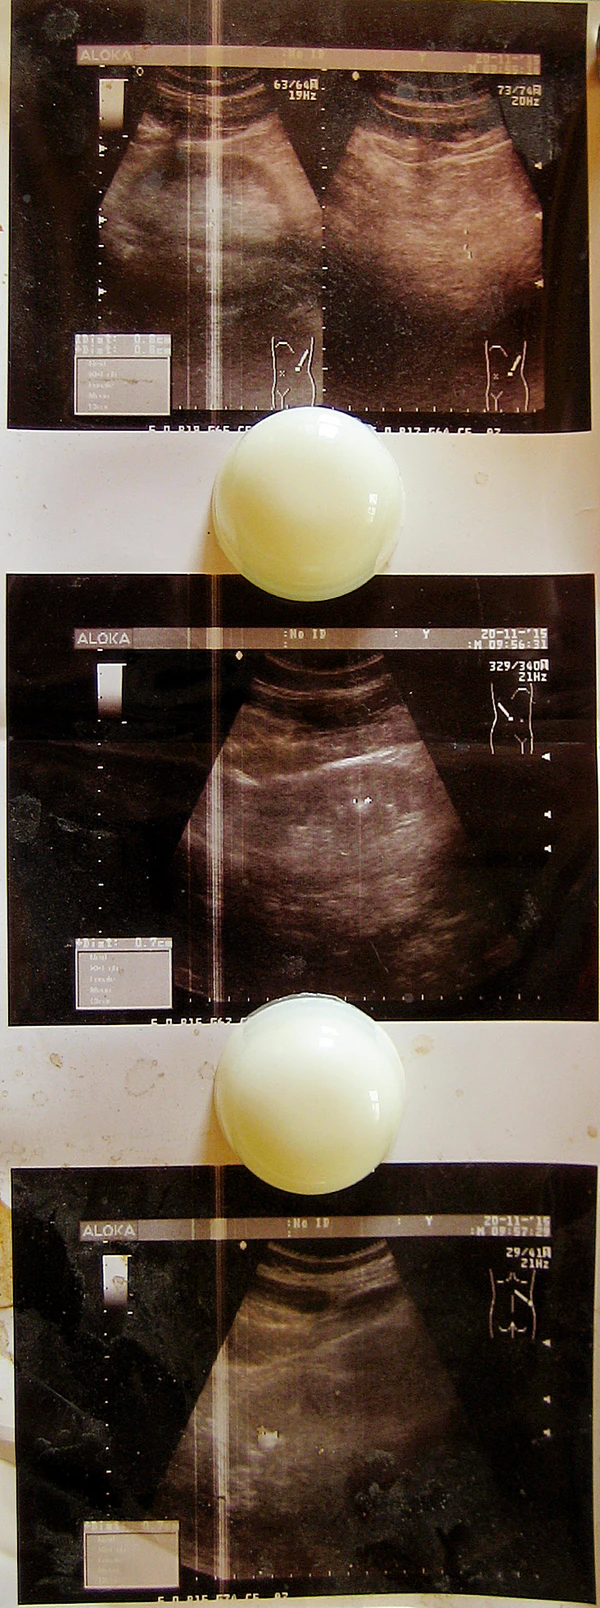

- Ультразвуковое исследование мочеполовых органов, позволяющее исключить сопутствующие заболевания;